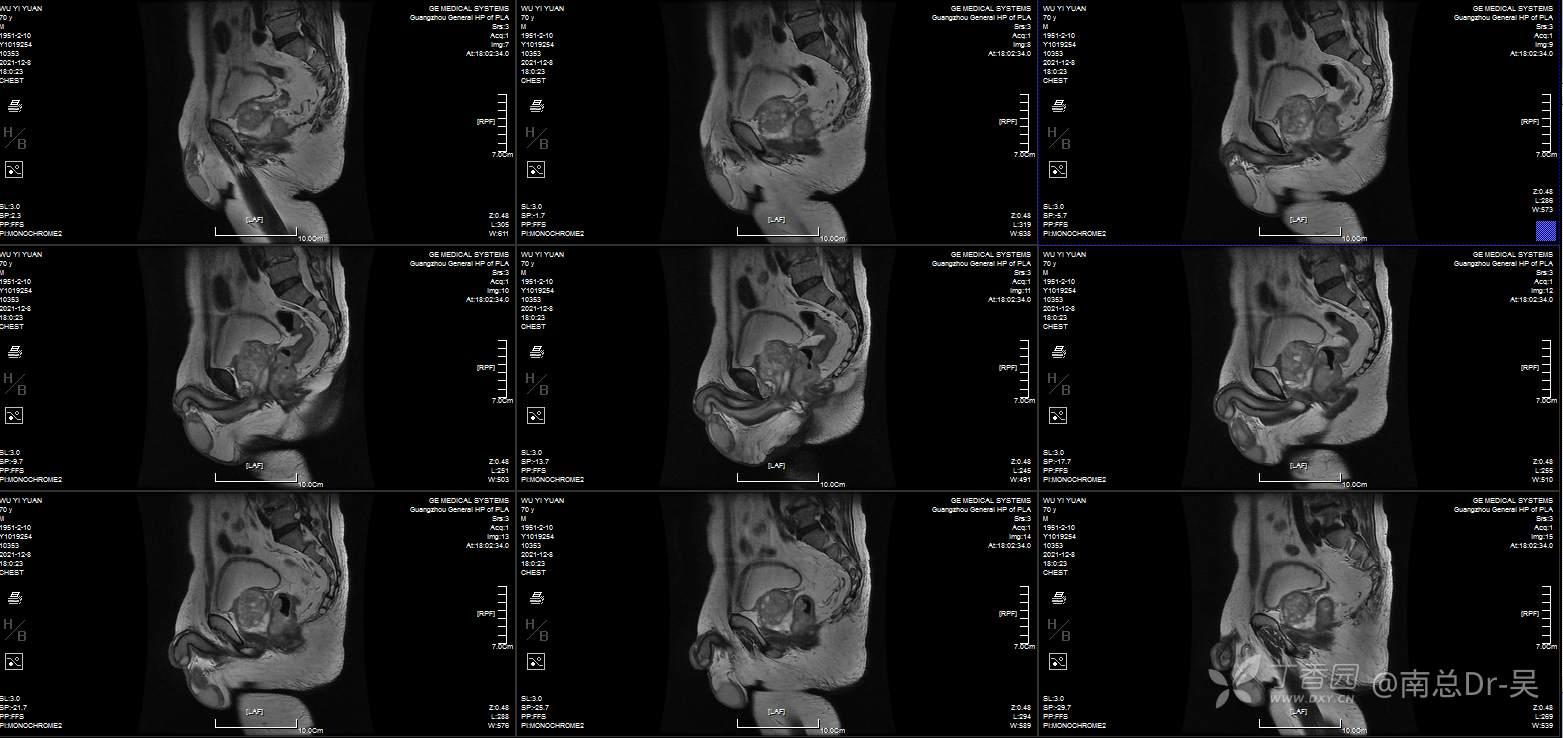

男性患者,81岁,诊断为:超低位直肠癌。肠镜提示距肛门2cm直肠占位,病理:中分化腺癌。患者本人有着强烈的保肛愿望,且评估该患者术前肛门功能良好,因此如何实施高质量的保肛手术是值得关注的问题。

低位直肠癌保肛手术方式多种多样,有ISR、TATME、Bacon、PAKS等等,但每一种手术有着其自身的优劣势,因此合适的手术是保证患者最大获益的前提。

直肠癌经肛拖出适形切除肛门功能重建术是一种两期法的手术,一期先经腹腔镜下直肠癌经肛外翻拖出切除,直视下适形切除肿瘤,尽量保留健侧的肛门括约肌。同时将近端结肠拖出至肛门外约4-6cm,待肠管与肛管自然愈合后约3周,局麻下行肠管切除、肛门整形术。

该手术其实是ISR+NOSES+BACON式的结合及改良,优势为“”“四无一有”腹部无切口、无引流管、无吻合口、无造口、有肛门功能。术后第1天即可恢复进食,符合ERAS理念,后续的辅助治疗可提前,术后5天可出院。

手术的技术要点在于腹腔镜下腹腔组的分离要达到括约肌间平面,肛门组经肛将直肠及肿瘤一起外翻拖出肛外,经肛门直视下适形切除病灶,遵循远切缘大于1cm的原则下,肿瘤侧多切,健侧多保留原则,目的是为多保留肛门括约肌,避免了以往的直线切除的健侧括约肌过多切除,影响术后肛门功能。残存的肛门外括约肌及耻骨直肠肌进行重建修复,重建新的肛直肠角,进一步改善术后肛门功能。近端结肠拖出长度以系膜松弛为原则,目的是为了预防术后早期出现的拖出肠管坏死,这方面技巧日后再说。最后二期的整形切除手术更需技巧,一是多保留粘膜,二是尽量切除增生的纤维瘢痕组织,三是缝合时带部分括约肌,达到缝合结束后粘膜是内翻,肛门外观良好。同时避免术后出现肛门狭窄、粘膜脱垂及少见的直肠漏。